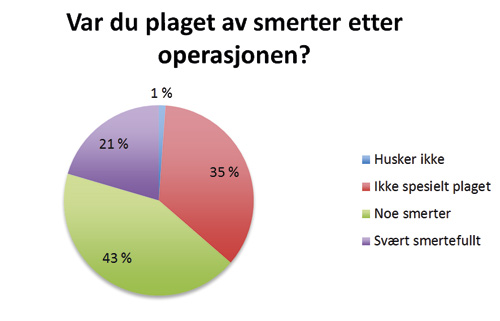

Var du plaget av smerter etter operasjonen?

Figur 3. Var du plaget av smerter etter operasjonen?

Den subjektive opplevelsen til pasientene etter behandling av palatinalt retinerte hjørnetenner ved lukket fremføring ble vurdert ut fra svarene fra spørreskjemaet som ble sendt til den enkelte pasient. Vi har ikke funnet noen tidligere studier hvor spørreskjema er benyttet i evaluering av denne type behandling. 90 % av pasientene var fornøyde med resultatet etter behandling. Vår studie viser også at pasientene stort sett er fornøyd uavhengig om pasienten har opplevd smerte under eller etter operasjonen. 20 % av pasientene som oppga at det var svært smertefullt under operasjonen oppga at de ikke var fornøyd med resultatet mot kun 4 % av dem som oppga noe smerter under operasjon. Blant de pasientene som synes at hele prosessen med å få dratt frem hjørnetann var veldig ubehagelig, er det overvekt av pasienter som er fornøyd med resultatet. At 39 av 47 pasientene var fornøyde selv om de svarte at de synes det tok lang tid, gjør at man kan anta at lang behandlingsperiode heller ikke er avgjørende for om pasienten blir fornøyd.

I forbindelse med vevsskade, som ved et kirurgisk inngrep som dette, vil pasientene kunne oppleve sensorisk og emosjonelt ubehag. At 6 % av pasientene opplevde at det var svært smertefullt under en slik operasjon, kan tyde på at det vil være behov for mer fokus på smertekontroll under operasjonene. 21 % av pasientene synes det var svært smertefullt etter operasjonen. Vi ser det er mulighet for at de forespurte pasientene ikke bare har svart om de opplevde postoperative smerter i forbindelse med selve inngrepet, men også om de opplevde smerter i forbindelse med kjeveortopedisk drag av tannen. Ettersom den kjeveortopediske delen av behandlingen også er forbundet med smerte, ser vi at det er behovet for mer nyanserte spørsmål for å få klarhet i dette. Det er også viktig å understreke at dette er en retrospektiv studie, og at det for mange av pasientene er opp til 6 år siden behandling ble utført.

I vår undersøkelse har vi ikke undersøkt smerter hos pasienter operert ved åpen fremføring, men en studie av Gharaibeh og Al- Nimri (9) har vist at de postoperative smertene etter lukket- og åpen fremføring av palatinalt retinerte hjørnetenner er sammenlignbare, men ved lukket fremføring var smertene av kortere varighet.